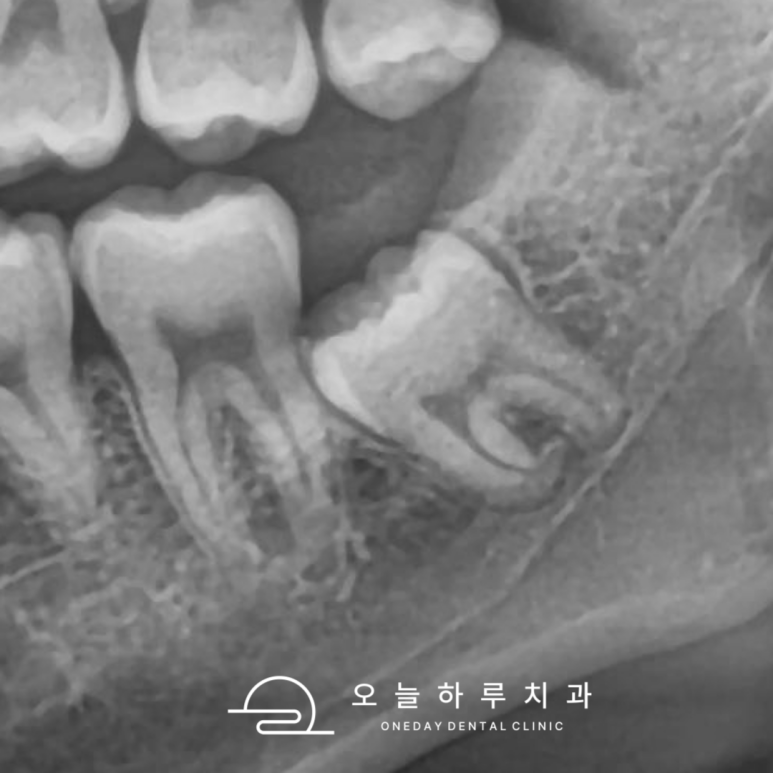

1. 옆으로 누워 난 매복 사랑니

사랑니가 옆 어금니 뿌리를 눌러

충치나 치근 흡수를 유발할 수 있습니다.

| 옆으로 누워나 발치가 필요한 사랑니 | 옆으로 누워난 사랑니를 발치하니, 앞 치아의 충치 발견 |

🔍 실제 사례: 옆으로 누운 사랑니로 인해

앞 치아에 깊은 충치가 생겨 신경치료까지 필요했던 경우가 있었습니다.